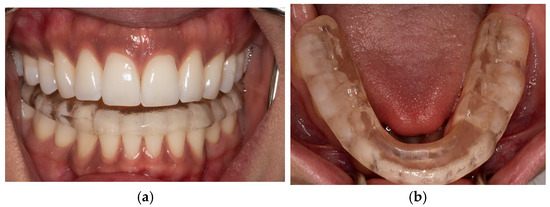

2.3. Controlled Mandibular Repositioning Method: Condylar Position Variator (CPV) (Gamma-Dental Klosterneuburg, Austria)

2.4. Controlled Mandibular Repositioning Method